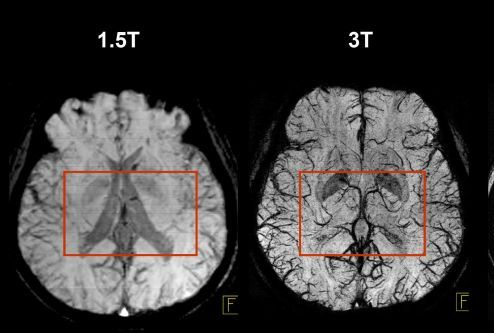

1.5 Tesla Imaging Method

1.5 T imaging uses a magnetic field strength of 1.5 Tesla. It is used for routine, whole-body imaging and is found in public hospitals:

Pros

is more tolerable for sick patients

less movement artefacts

safer

3 Tesla Imaging Method

3 T Imaging uses a magnetic field strength of 3 Tesla and is high resolution imaging.

Pros

has more signal

decreased scan time

Cons

More chance of burns and projectiles

Harder for patients to thermoregulate so increased movement